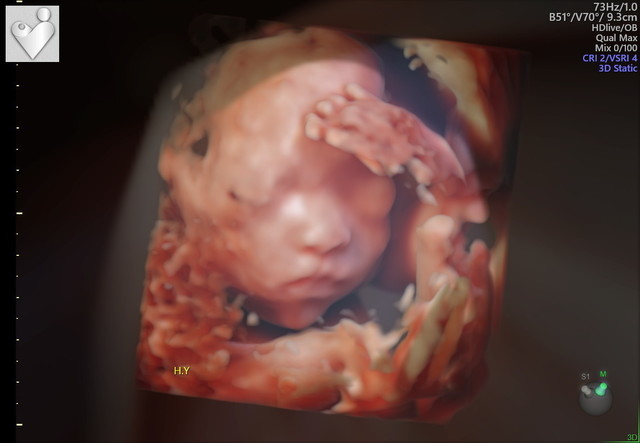

エコー写真撮影時のエピソード(妊娠16週目:16w0d)

まさかの足での敬礼。産婦人科の先生も、足で敬礼してる子はなかなかいないねって笑ってました。もっと前に撮ったエコーではここまで顔立ちハッキリしてなくわからなかったですが、、この時のエコーは鼻と口元が主人にそっくりでびっくり。主人に「似てるね」って話したら、「そうかなぁ?」って照れながら喜んでました。

まさにこれ「ブンブンハローユーチューブ」でお馴染みyoutuberのHIKAKINのポーズにそっくり!しかもこちらの赤ちゃんは足で行ってるなんて!将来は大物!?